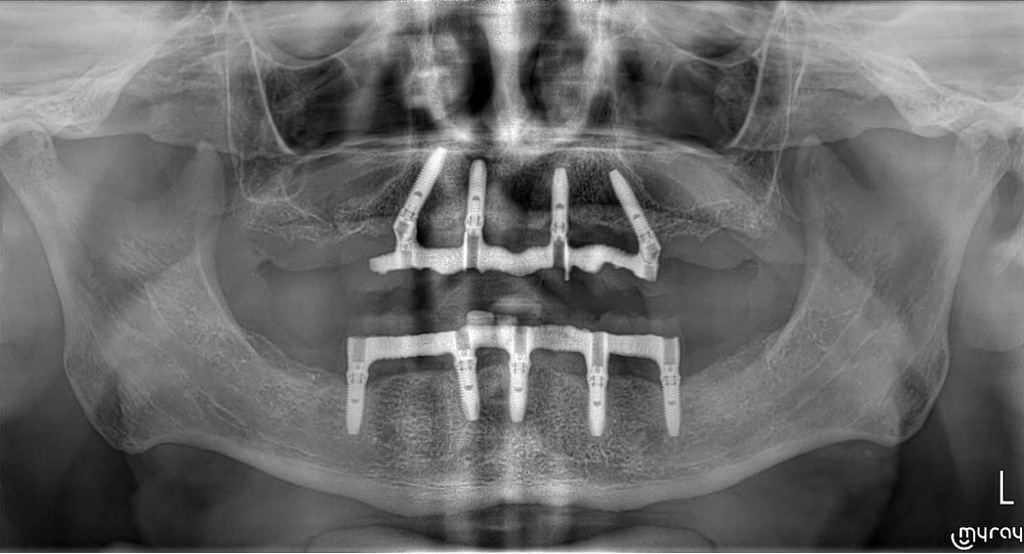

Gli impianti hanno il compito di sostituire uno o più denti mancanti, fino ad un’edentulia completa, e di servire da sostegno per una protesi ad essi ancorata.

Allo Studio Ragazzini sappiamo gestire al meglio il tessuto osseo, che costituisce il sostegno dell’impianto, e siamo in grado di ricostruire tale tessuto nel caso esso venga a mancare, anche in situazioni molto complesse.

Le tecniche che utilizziamo sono sviluppate per rispondere al meglio alle vostre esigenze: invasività della chirurgia ridotta al minimo, nessun taglio della gengiva, chirurgia software guidata e carico immediato sono solo alcuni degli accorgimenti studiati per ridurre al minimo i disagi legati alla chirurgia.